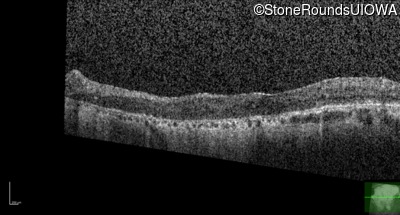

Foveal Hypoplasia (IIIG)

Diagnosis & molecular findings

Disease Gene Allele 1 variant(s) Allele 2 variant(s) Inheritance mode

Foveal Hypoplasia PAX6 Pro76Leu CCG>CTG   AD